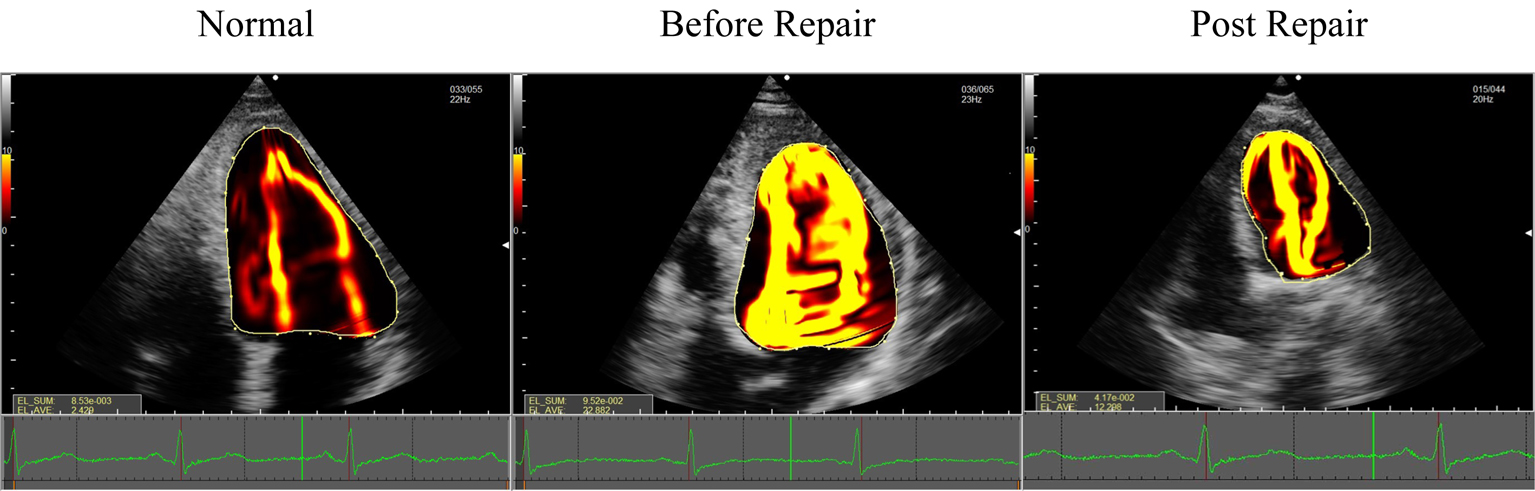

Fig. 3.EL-AVE in patients who underwent mitral valve repair and controls. EL-AVE of patients after mitral valve repair was higher than that of controls. EL-AVE, average energy loss.

Compared with the control group, the EL-AVE before and after operation in the

mitral valve repair group was significantly increased (p

Compared with one week before operation, the EL-AVE after operation in the

mitral valve repair group was significantly decreased (p

Mitral valve repair has become the preferred surgical procedure for the treatment of patients with severe degenerative mitral regurgitation [16, 17]. The procedure involves partially resection of the posterior mitral leaflet and implantation of a mitral annuloplasty to reshape the annulus and support leaflet repair [18]. The changes in the spatial conformation of the annulus and elevated mitral gradients lead to a change of LV flow pattern and affects the prognosis of patients [19]. Morichi et al. [20] reported that energy loss after mitral valve repair was greater than that of healthy volunteers during early diastole, as measured by VFM. This may be due to a different type of annuloplasty ring that was used during mitral valve repair. The relatively small ring resulted in an abnormal LV flow pattern and increase in energy loss.

Our study has two main findings. First, the EL-AVE in patients after mitral valve repair was higher than that of controls, but lower than that before mitral valve repair. Second, mitral valve repair resulted in a higher EL-AVE in patients with resected leaflets than in those with unresected leaflets while the same type of annuloplasty ring was used.